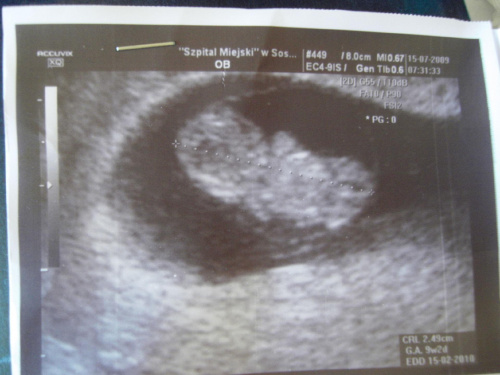

To nasza Dziewczynka;-)